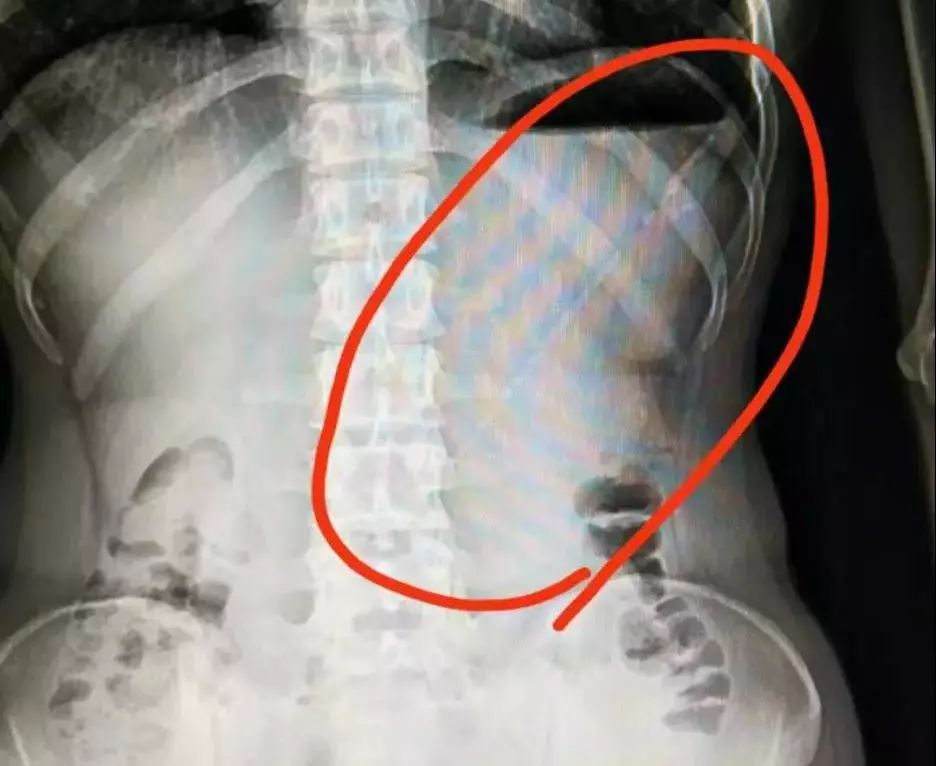

最后,南方医科大学深圳医院普外科的医生们,联合麻醉科、消化内科、手术室等一起,顺利将异物取出。

当这根条状物揭开它神秘的面纱时,在场所有的医生恍然大悟:原来是你啊,牙签!

▲ 手术取出来的牙签

而且,哪怕“进驻”了这么久,这根牙签依然保留着它原来的面目,两头尖,长度有 6.3cm!